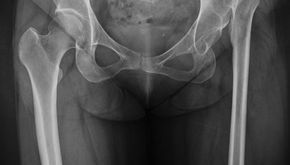

人工關節手術多半能大幅改善生活品質,但如果不幸發生慢性人工關節感染(Chronic Periprosthetic Joint Infection, PJI),治療就會變得相當棘手。特別是當感染時間拉長、變成「慢性」時,單靠抗生素幾乎無法根治。在這種情況下,兩階段翻修手術(Two-Stage Exchange Arthroplasty),長期以來被認為是治療慢性人工關節感染最可靠、最成熟的方法,也常被視為標準治療策略 [1–4]。 什麼是「兩階段翻修手術」? 顧名思義,這是一種分成兩次手術完成的治療方式,目的只有一個: 👉 徹底清除感染,讓人工關節有機會安全地重新裝回去。 🦴 第一階段:清除感染源 第一階段手術的重點包括: 移除已感染的人工關節 徹底清創,把被細菌污染的組織清乾淨 放入一個含抗生素的骨水泥間隔物(antibiotic-loaded cement spacer) 這個抗生素骨水泥間隔物可以: 局部釋放高濃度抗生素 維持關節空間,避免軟組織攣縮 讓病人在等待期間仍保有一定穩定度 手術後,病人會接受針對細菌種類量身訂做的抗生素治療 [